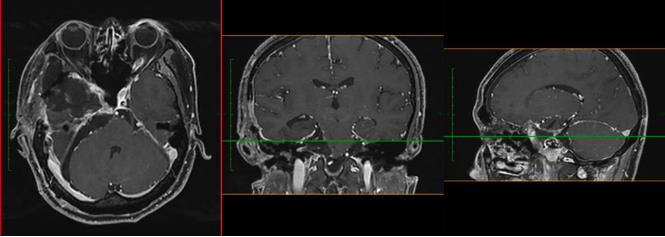

當(dāng)?shù)蒯t(yī)院對(duì)小成頭顱進(jìn)行MRI檢查,提示:鞍區(qū)、中顱窩及后顱窩巨大占位,腦干受壓明顯,且部分已侵襲突破顱底骨質(zhì),腫瘤大小約8.2*7.3*5.8cm,此外,電子視野檢查發(fā)現(xiàn)右眼鼻側(cè)視野、左眼顳側(cè)視野嚴(yán)重缺損。